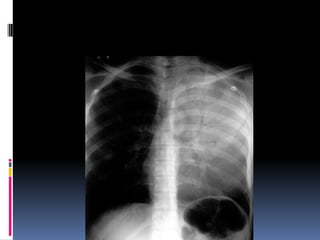

Underpenetrated Film

Hemi diaphragms are obscured

Pulmonary markings more prominent than they actually

Underpenetrated Film Hemi diaphragmsare obscured Pulmonary markings more prominent than they actually